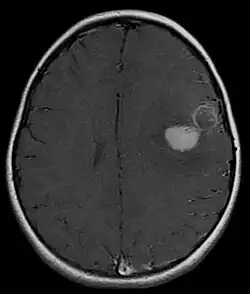

Tumeur neuroectodermique primitive du système nerveux central

Une tumeur neuroectodermique primitive (PNET) du système nerveux central fait habituellement référence à une tumeur neuroectodermique primitive supratentorielle :